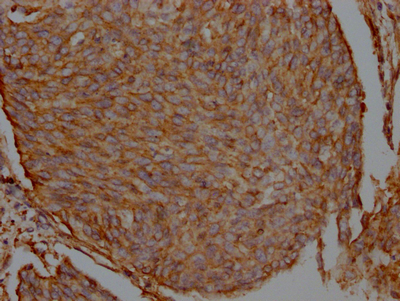

IHC image of CSB-RA548809A0HU diluted at 1:100 and staining in paraffin-embedded human cervical cancer performed on a Leica BondTM system. After dewaxing and hydration, antigen retrieval was mediated by high pressure in a citrate buffer (pH 6.0). Section was blocked with 10% normal goat serum 30min at RT. Then primary antibody (1% BSA) was incubated at 4℃ overnight. The primary is detected by a Goat anti-rabbit IgG polymer labeled by HRP and visualized using 0.05% DAB.